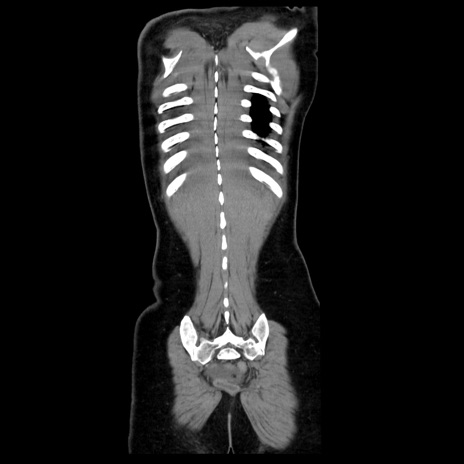

症例39(冠状断像)

【症例】40歳代女性

【主訴】上下腹部痛

【現病歴】2日目から下腹部痛あり。夜間は痛みで眠れなかった。昨日より上腹部痛と下痢が出現。臥位で痛みは軽快したため、休んでいた。本日になって臥位でも立位でも痛みが強くなってきたため救急要請。

【既往歴】子宮内膜症

【身体所見】部:平坦・軟、左上下腹部に圧痛あり、反跳痛あり。

【データ】WBC 21800、CRP 26.78

CT